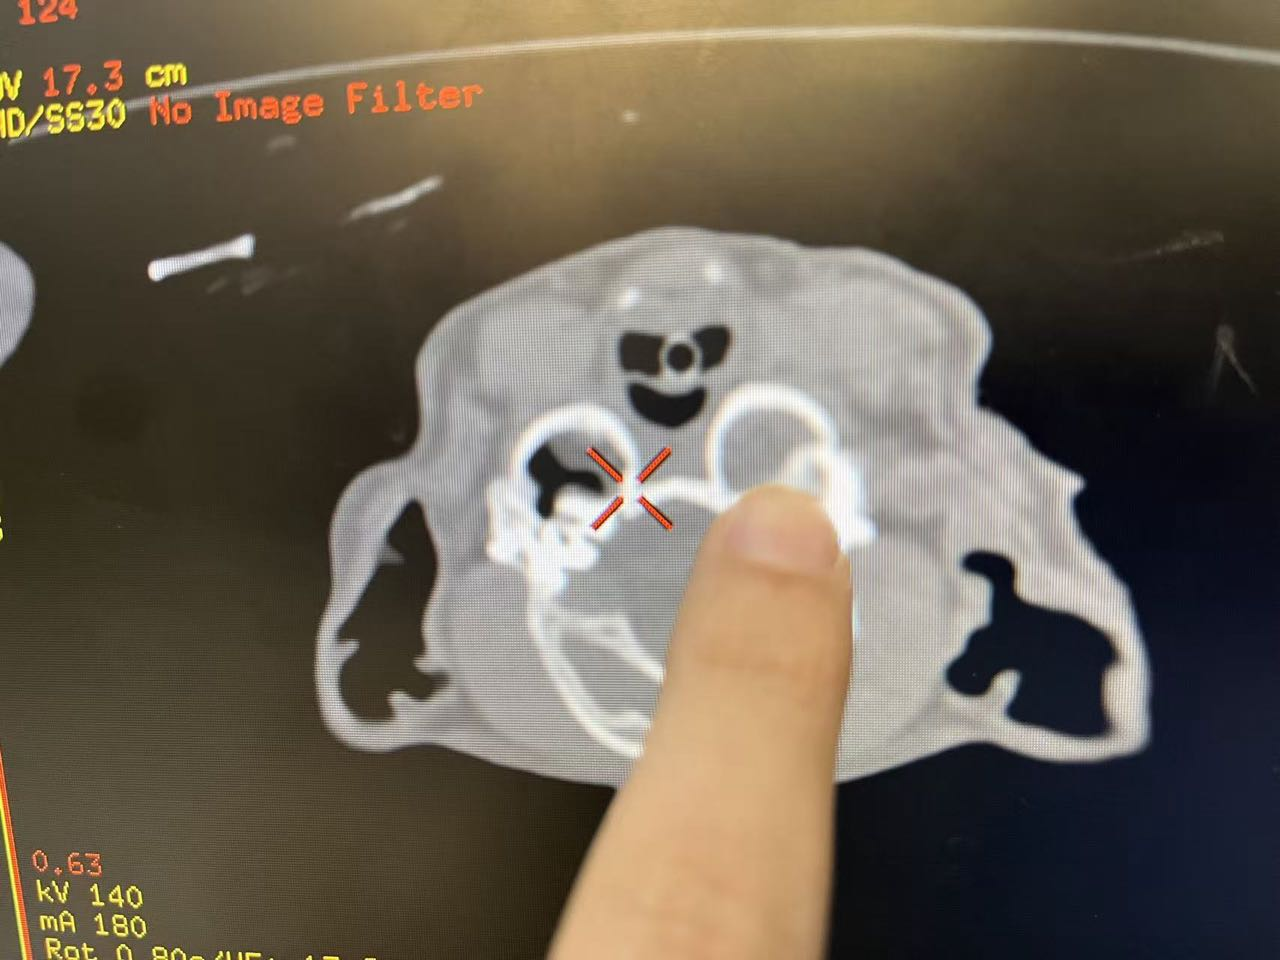

接诊的耳鼻喉专科负责人叶精精医生通过耳镜检查发现其左耳存在大面积溃疡性损伤,脓性分泌物充斥耳道。为进一步明确病因,医院立即协同CT影像科及实验室进一步检查:CT影像检查显示其存在双侧严重中耳炎,中耳腔内积液、肉芽组织与炎症碎屑大量蓄积,鼓室骨质出现溶解迹象;同时伴左侧外耳炎、牙齿/颞颌关节结构异常,需排除肿瘤转移及肝脏病变;实验室病原学检测检出耐药性强的铜绿假单胞菌;组织病理学分析则确诊中耳炎性息肉及肉芽组织阻塞耳道,导致脓性分泌物引流不畅,成为长期不愈的关键诱因。